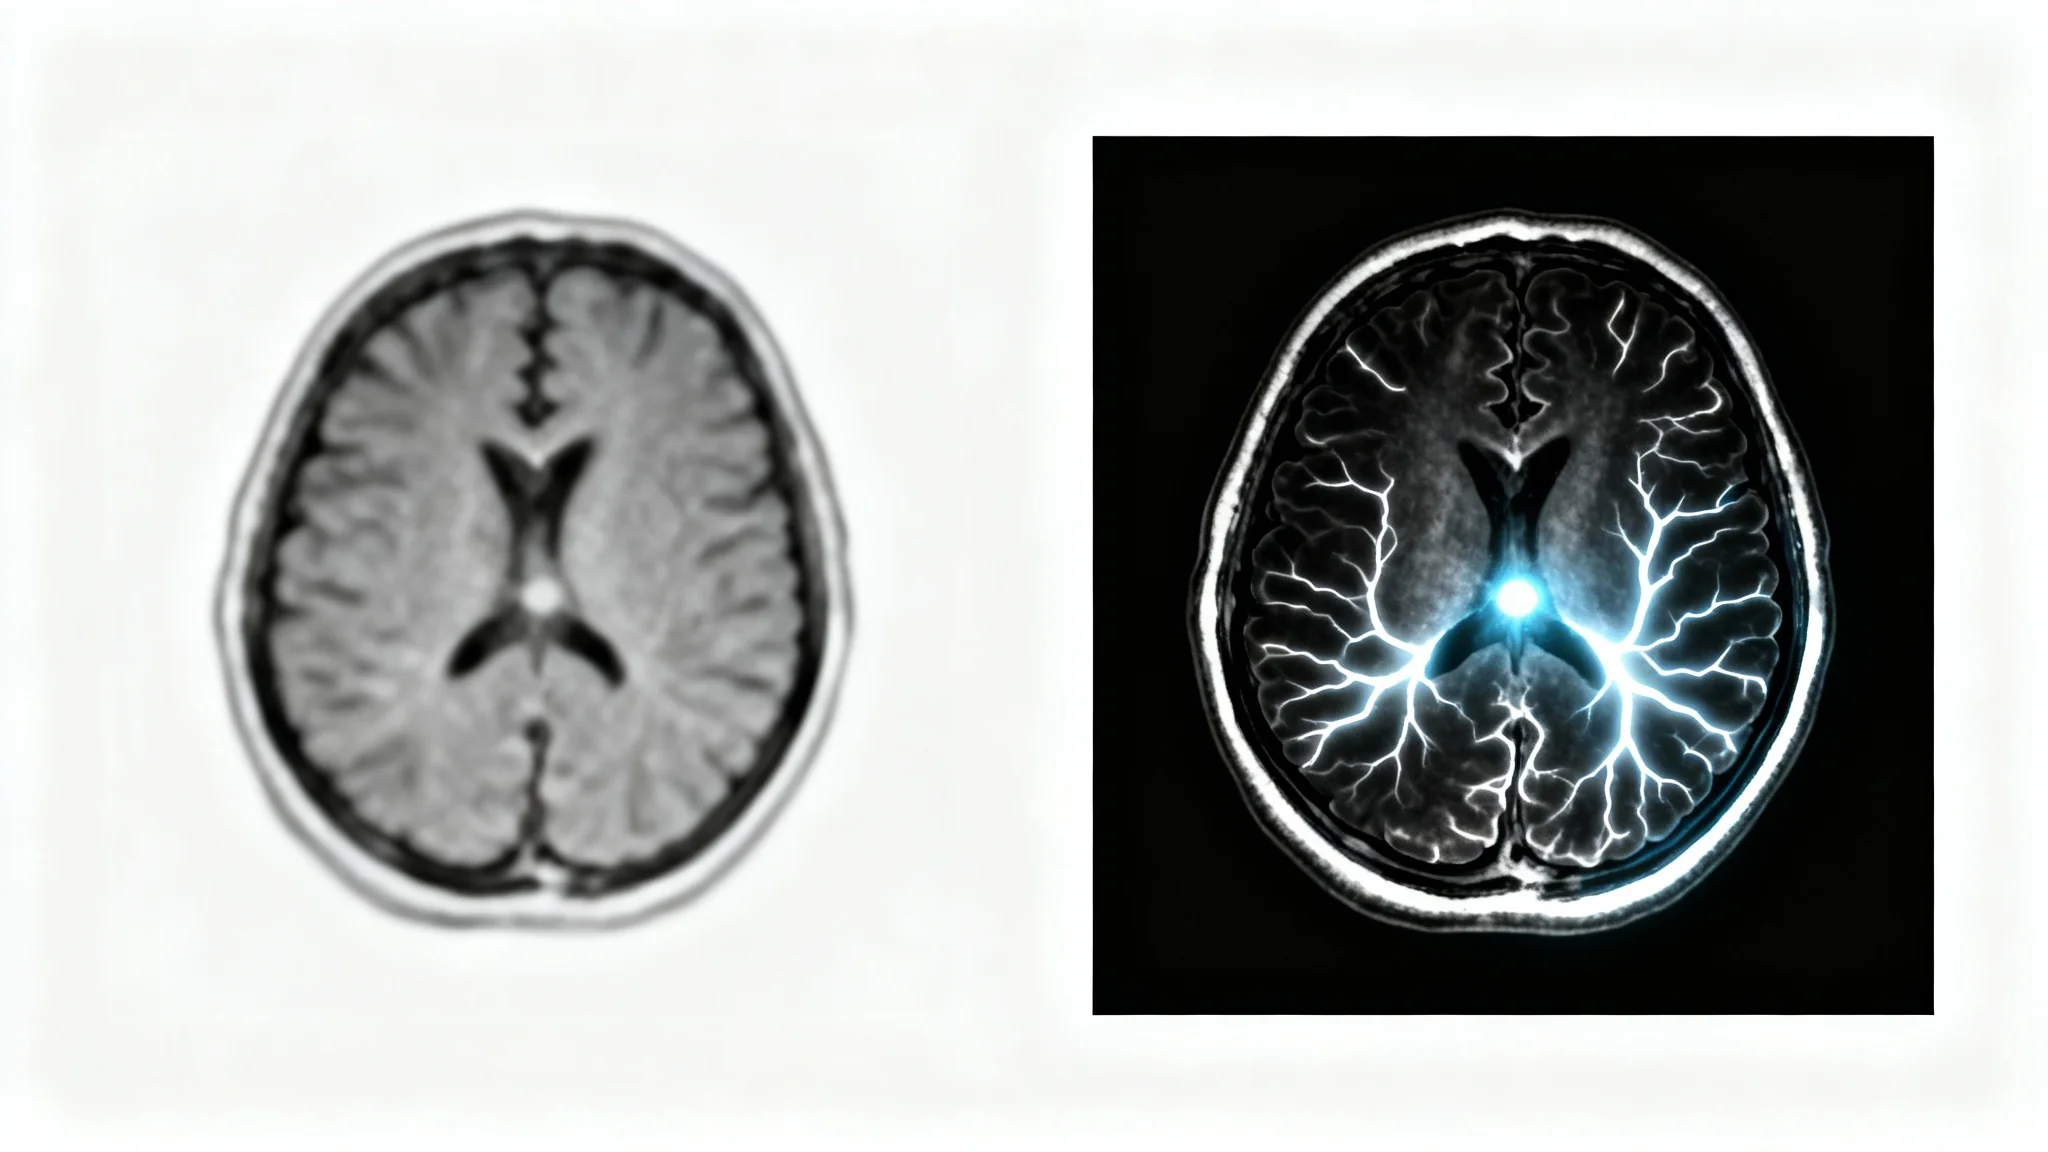

A side-by-side comparison of a human brain MRI. The 'before' image on the left is low-contrast and indistinct, while the 'after' image on the right is sharp and clear, illustrating the effect of contrast enhancement technology.

It's Fast: Go from a raw scan to an enhanced, analysis-ready image in seconds. It’s Precise: AI algorithms are trained to identify and enhance medically relevant features with high accuracy. It's Simple: No complex software to install. Just upload your scan, enter a simple prompt, and generate. It's an Assistant: The tool acts as a powerful assistant for radiologists and researchers, helping to highlight areas of interest and improve workflow efficiency. It’s Versatile: Use it to enhance a wide range of MRI scans for various clinical and research applications.